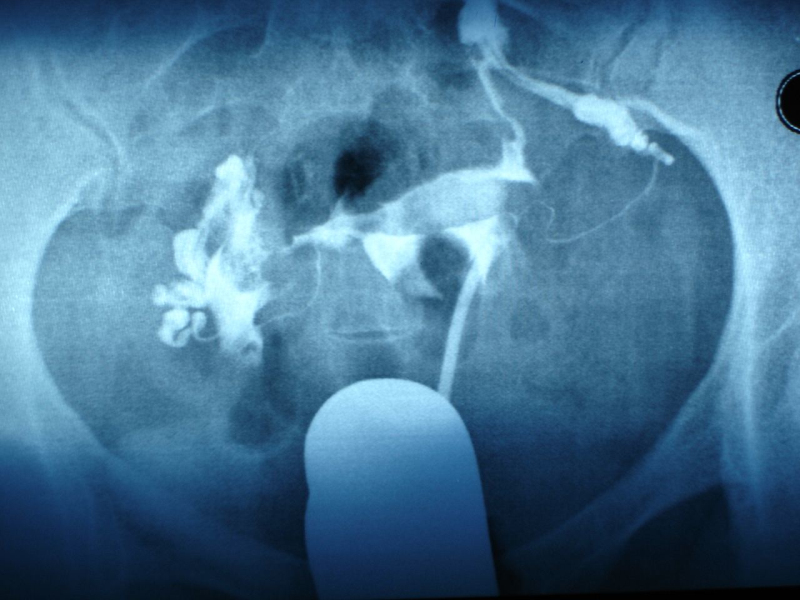

首先,产科大夫会把手从产道中伸进去,伸到子宫中,几乎半只胳膊就进去了,摸到胎盘附着的位置。

然后,产科大夫会用另一只手压住妈妈的肚子,扶好不让胎盘的位置乱动,然后用手指沿着胎盘和子宫附着的位置一点点抠出来。如果顺利的话,整个胎盘能全部取出。

把大块胎盘取出后,接下来,手还要伸进子宫,再去摸一遍,检查子宫壁上是否有胎盘的碎片残留,因为必须要清理的干干净净。